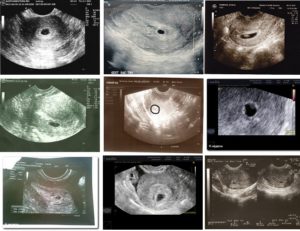

Чтобы исключить такое состояние, даже после получения положительного результата теста на беременности, стоит записаться на ультразвуковое исследование. Обычно оно проводится вагинально при помощи специального датчика.

Но так как многие женщины бояться, что такое обследование вызовет выкидыш, можно записаться на УЗИ на полный мочевой пузырь.

В таком случае врач-узист сделает процедуру абдоминально, что означает проведение процедуры на поверхности живота при помощи небольшого датчика и специального геля.